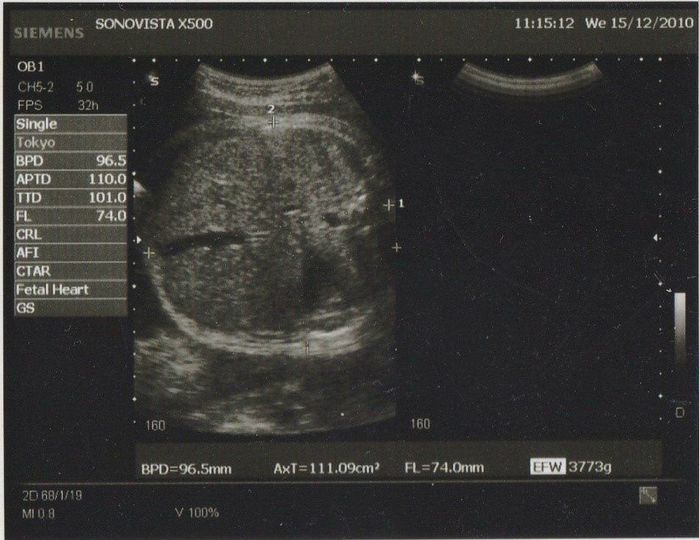

妊娠40週目のエコー写真

待ちに待った予定日にしたエコー検査です。頭部しか写っていませんが、なんとビックリ! 推定体重は3773g! おなかも大きめスイカがはいっているかのように特大サイズになっていて、歩くのもつらかった最終幕でした。